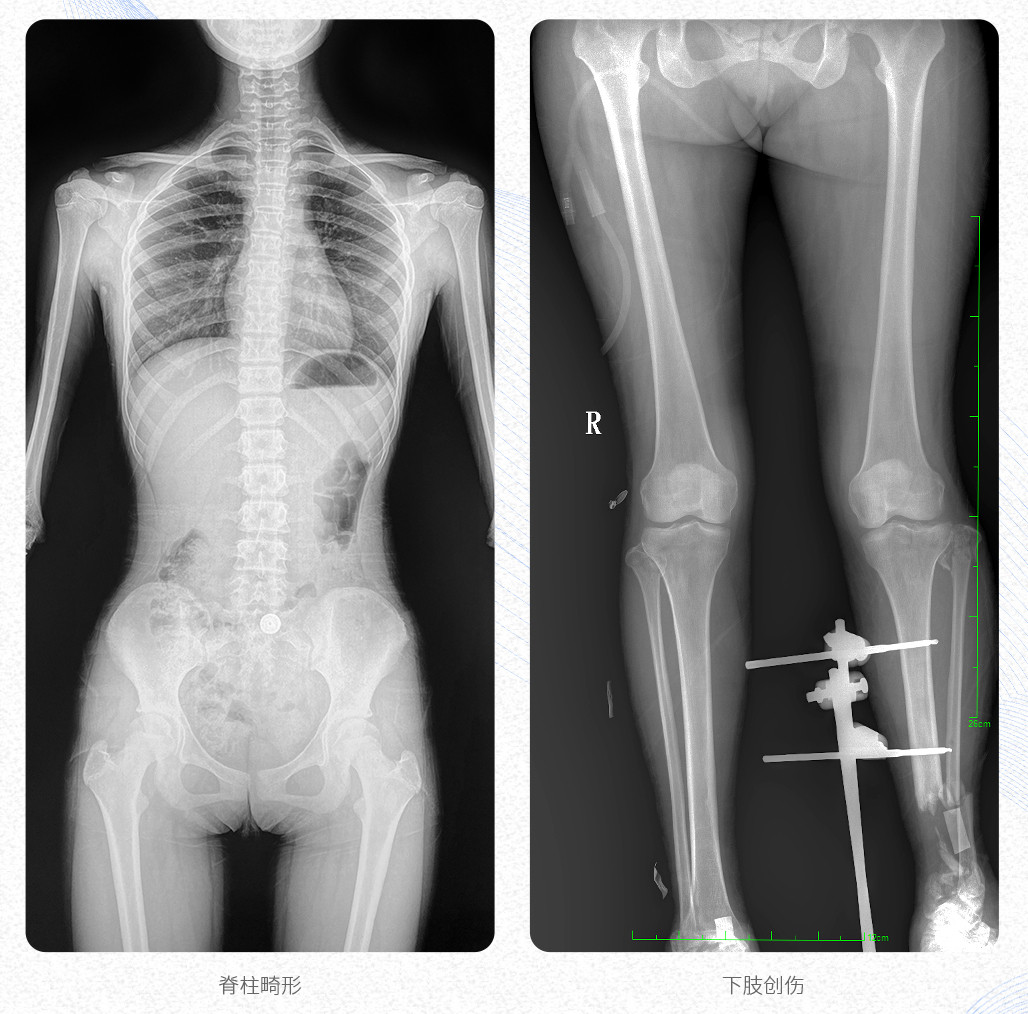

臨床應用:支持全脊柱攝影、雙下肢攝影、脊髓造影、復雜創傷、人工關節置換、關節損傷的修復重建等大視野臨床應用。

17"*34"有效視野,是市面大尺寸平板的2倍,一次成像不拼接。相較于多張攝影再軟件拼接的DR設備,PLX8600解決了拼接圖像存在密度不均勻,拼接處圖像配準和放大效應等問題,給臨床帶來了真正的大視野影像解決方案,高清畫質,準確成像不失真,可一次性覆蓋全脊柱或雙下肢影像。PLX8600大視野平板動態DR攝影速度快,患者可以更快的完成檢查,且單次攝影輻射劑量是常規多張攝影再軟件拼接DR的1/2或1/3,低劑量給患者更多關愛。

PLX8600大視野平板動態DR可在低輻射劑量下獲得患者站立位、臥位的高質量影像。搭載自主研發的圖像均衡處理系統,能夠很好的均衡人體不同厚度組織的影像,視野大,圖像清晰,層次豐富。